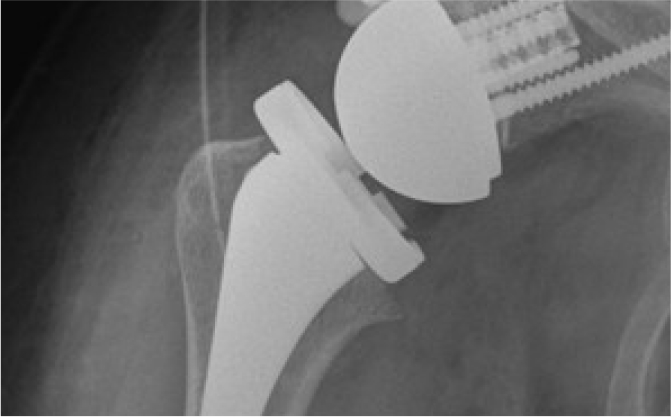

어깨 관절을 이루는 뼈의 끝에는 연골이 있어

부드럽게 움직이도록 도와주는데, 이 연골이 마모되거나 손상되면

뼈끼리 마찰이 생기고 염증 및 통증을 유발하게 됩니다.

증상이 서서히 진행되며 악화되기 때문에 조기 진단과 치료가 중요합니다.